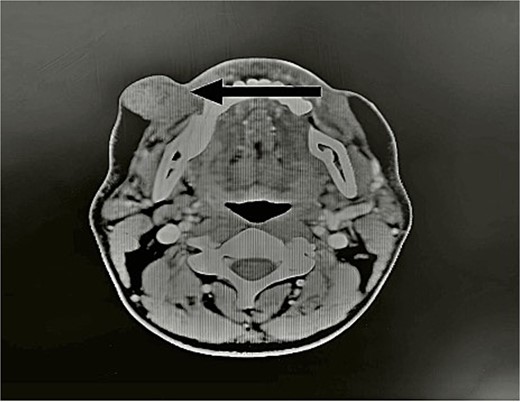

A 39-year-old man presented for evaluation of a painless, firm right cheek mass that had been growing slowly for the past year. He denied any history of discharge, pain, or numbness. The examination revealed a movable right cheek mass next to the oral commissure, measuring 4 x 3 cm. No overlying skin changes or buccal mucosa changes were noted. The rest of the examination of the head and neck was unremarkable (Fig. 1).

Image showing the mass on the right cheek region (arrow pointed to the mass). The mass was ~4 cm by 3 cm in size, painless, firm, and mobile.